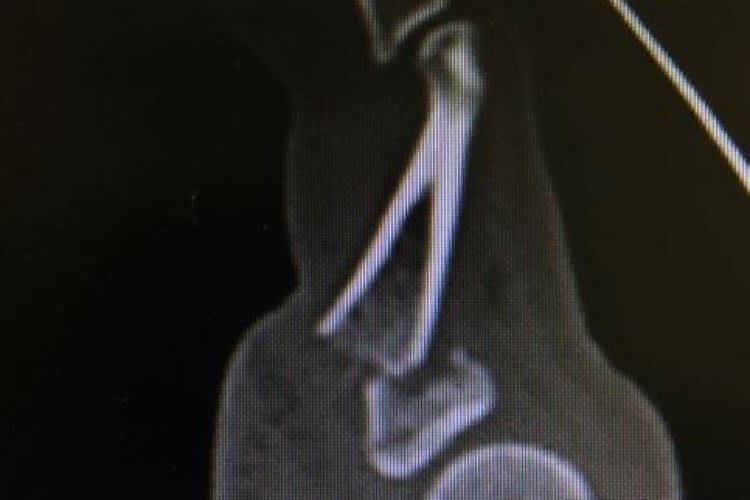

Dabei wurde entdeckt, dass sich Sykes nicht nur den fünften Finger gebrochen hatte, sondern auch den vierten sowie das Handgelenk. Somit war eine Rennteilnahme des 32-Jährigen unmöglich. Der Eingriff dauerte zwei Stunden, bei dem der fünfte Finger mittels einer Metallplatte fixiert wurde. "Die Ärzte scheinen mit dem OP-Verlauf zufrieden zu sein", sagte Sykes aus dem Krankenbett. "Es war ein schlimmer Bruch. Im Finger daneben war ein Riss und auch an der Speiche, unmittelbar am Handgelenk. Eine solche Verletzung hatte ich schon einmal und bin dennoch nach vier Tagen auf Phillip Island die Rennen gefahren. Ich muss abwarten, wie es dieses Mal funktioniert." Im günstigsten Fall sprachen die Ärzte von einer vergleichsweise kurzen Genesungszeit. Die Teilnahme am Meeting in Magny-Cours könnte möglich sein.